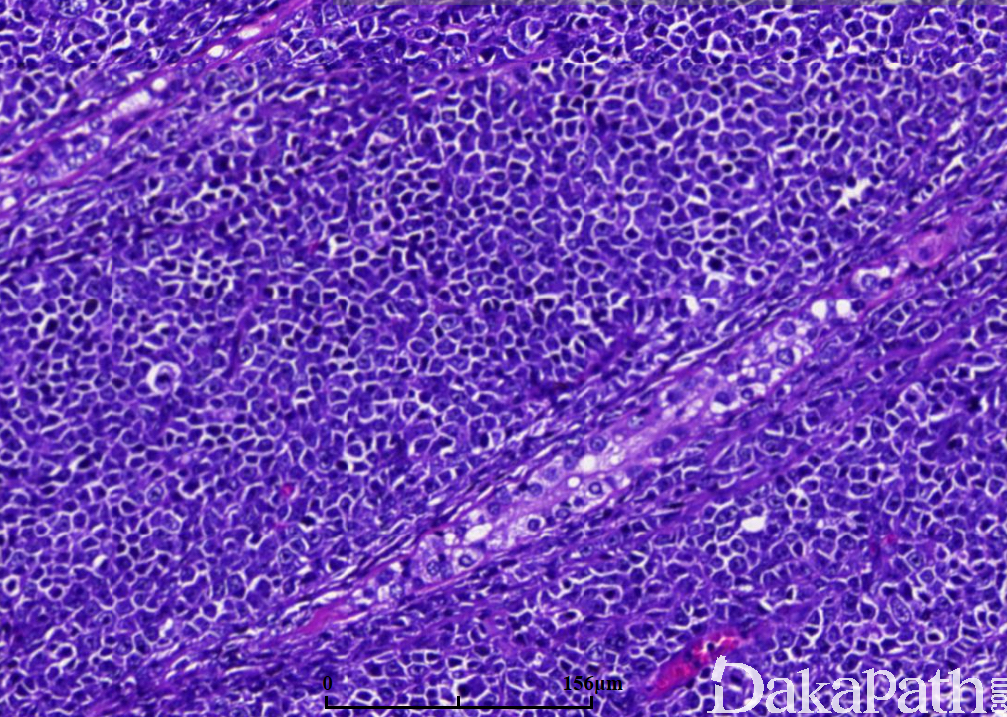

镜下肿瘤中央区域曲细精管消失,周边区表现为曲细精管间浸润,并浸润曲细精管;

肿瘤由大的淋巴细胞构成,圆形或卵圆形,核形不规则,偶尔可见分叶核,核仁清楚,胞质稀少;